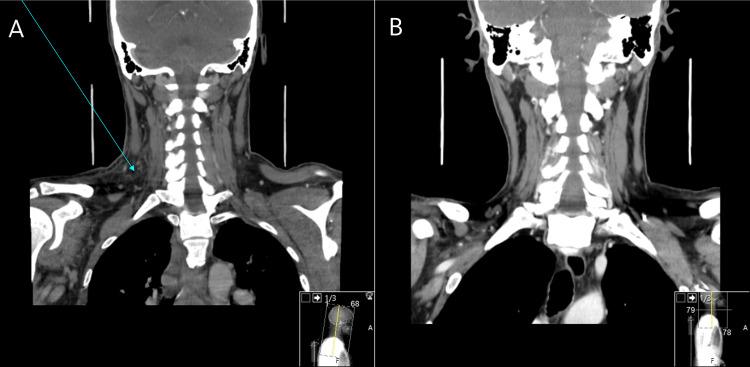

We report the case of a man in his 50s with refractory acute myelomonocytic leukaemia (AML) who presented with neck swelling, fever, and elevated levels of C-reactive protein (CPR) after venous punctures. An infected haematoma was presumed, but the patient showed no signs of improvement under broad-range antibiotics, and microbiological results were negative. The subsequent development of a rapidly evolving erythematous-violaceous plaque around a site that had previously punctured on the extensor surface of the right arm prompted us to reconsider the clinical setting as a whole and consider the hypothesis of deep neutrophilic dermatosis (ND) associated with haematologic malignancy. A biopsy of the arm lesion showed an aseptic neutrophilic infiltrate, confirming this diagnosis. The patient was initially treated with high-dose intravenous corticosteroids, resulting in a dramatic improvement of the skin lesions.

我们报告了一例50多岁患有难治性急性粒单核细胞白血病(AML)的男性病例,该患者在静脉穿刺后出现颈部肿胀、发热和C反应蛋白(CRP)水平升高。推测为感染性血肿,但患者在使用广谱抗生素治疗下未见改善迹象,微生物学检查结果为阴性。随后,在右臂伸侧先前穿刺部位周围迅速出现一个不断演变的红斑紫罗兰色斑块,促使我们重新审视整个临床情况,并考虑与血液系统恶性肿瘤相关的深部嗜中性皮病(ND)这一假说。对手臂病变进行活检显示为无菌性嗜中性粒细胞浸润,从而证实了这一诊断。患者最初接受大剂量静脉注射皮质类固醇治疗,皮肤病变得到显著改善。